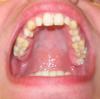

Здравствуйте уважаемые врачи, вот уже год назад задался целью хоть немного улучшить вид своего забора, т.к. тошно на себя смотреть. Побывав у нескольких врачей ортодонтов, диагноз был поставлен как глубокий дистальный прикус, узнав цены на лечение, решил подождать и собрав бюджет, решился, но потом моё мнение к обычным т.е. наружным брекетам изменилось, и стало вызывать у меня комплексы (тут ничего не поделаешь) и принял для себя решение более дорогое лечении в виде брекетов Инкогнито, чисто психологически мне так проще я думаю. У нас в городе лингвальным брекетами Инкогнито никто не занимается, поэтому собираюсь поехать в Санкт- Петербург. Поэтому уважаемые доктора прошу посоветовать хорошего ортодонта для лечения. Теперь касательно моего прикуса и забора в целом. У меня вопрос, в каких случаях удаляются зубы? Т.к. одни ортодонты лечат с удаление, другие без, ведь наверно каждому пациенту хотелось бы по возможности оставить свои зубы, коих осталось и так мало...увы. Меня напугали на одном сайте тем что такой вид патологии как у меня лечится только хирургическим вмешательством, что меня шокировало, т.к. на такое я вряд ли смог пойти. Только прошу не пугаться:) таких картин, но что поделаешь.